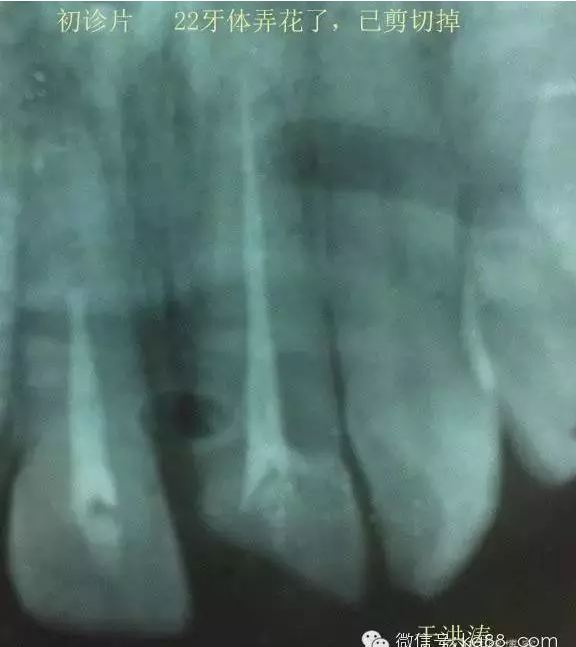

輔助檢查:X線片檢查11 22牙冠均有缺失。11 21 22 髓腔內(nèi)均有充填物,11充填不到位, 21充填不實,22充填到位髓腔高密度影像。11 21 牙周膜有增寬,21根尖區(qū)有2mm左右低密度影像。未發(fā)現(xiàn)有牙根側(cè)穿或斷裂異物。

輔助檢查:插針X線片顯示根管內(nèi)充填物已經(jīng)取出。試尖片顯示牙膠尖未到位,繼續(xù)用K銼和機括向根尖預(yù)備。根充結(jié)束片顯示根充密實,無超充,無欠充。